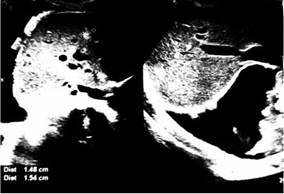

Se completó el estudio con ecografía abdominal, que evidenció múltiples nódulos hepáticos (Figura 2). La ecografía renal y vesical mostró una lesión medular derecha de aproximadamente 7 cm, sugestiva de proceso neoplásico (Figura 3).

FIGURA Nro.2: Ecografía de rastreo abdominal que muestra hígado de tamaño normal con varias lesiones focales hiperecogénicas redondeadas de hasta 2,5 cm de diámetro, incidentalmente se observa implantes pleurales metastásicos.